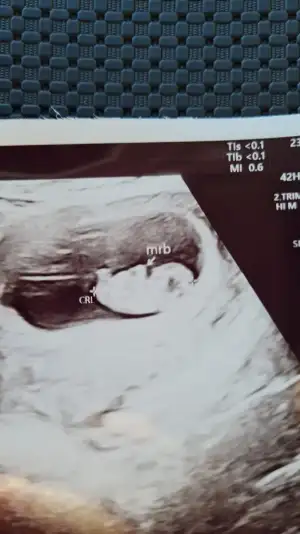

Canım nub a göre cinsel organı oluşturan yapı yatıksa kız deniliyor, senin minnoşun da yatık gibi ama alnı da erkek gibi😊 nub bilmesem erkek derdim.

Canım tarama testinde karşıda monitörden gösteriyordu doktor nub dediginiz yeri bacakları olarak gösterdi.bu arada Rabbim önce sağlıklı sonra hayırlı evlat olmasını dilerim.hazirda iki kızım iki oğlum var eşitliği kim bozacak meraktayım 🤭 eşim erkek hissediyorum diyor ben hiç birşey 😅birde eşimin alın önde açık çene uzun ve sivri yapısal olarak benim yüzüm oval ve uzun.

Kızlar yüklemeyi başarabildiysem bana da cinsiyet yorumu yapabilir misiniz :) ilk bebeğimiz 8+6 idi 9+1 gözüktü ultrasonda :)

Kızlar birde nub teorisi mi var:emir_bebek: Bilenler bize de bir tahmin de bulunabilir mi:) 11+3 idik bir hafta önden gidiyormuşEki Görüntüle 2789737

Canım nub pek belli olmuyor gördüğüm o ise kız gibi 30 derece altında :)) yaa inşallah 12.hafta bende böyle bir şey görürüm bin kere maşallah canım. 💙